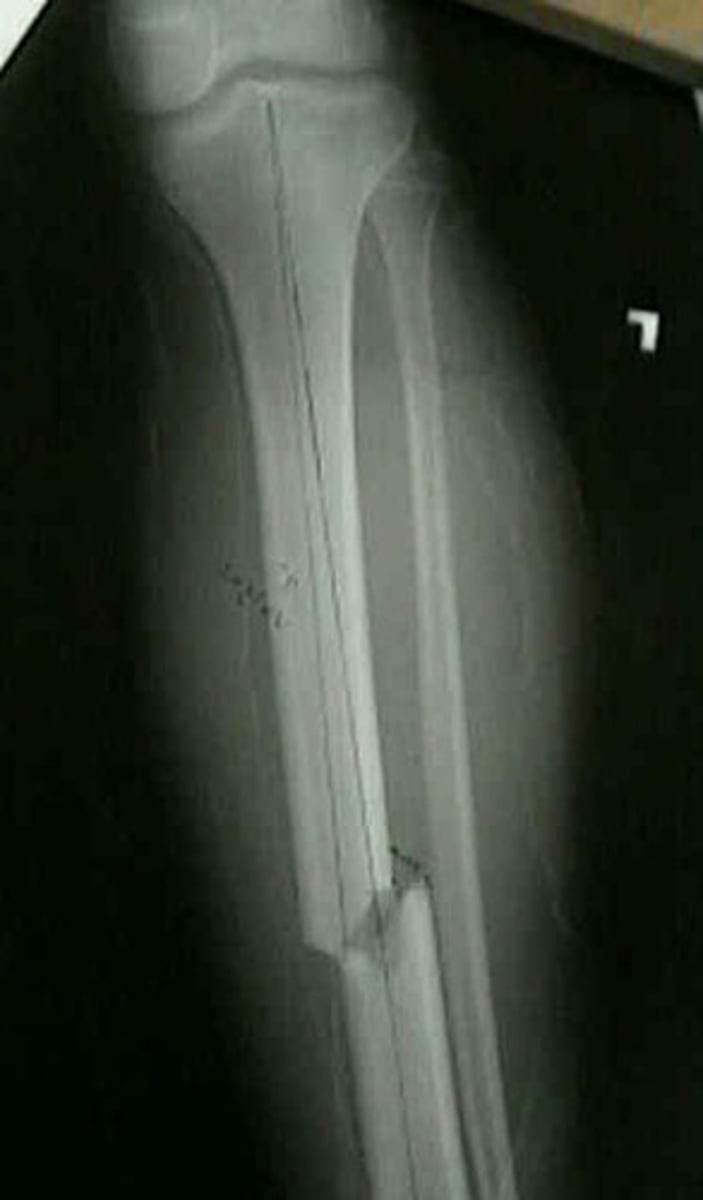

transverse fracture line

fracture is perpendicular to bone axis

spiral fracture line

torsional fracture that spirals around bone, often due to twisting

linear/longitudinal fracture line

fracture is parallel with axis of bone